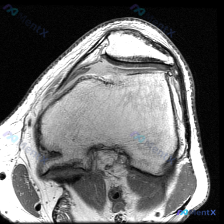

刚整理完这份膝关节MRI的读片思路,这个病例其实挺有代表性,很容易犯锚定错误,分享给大家一起看看。 病例基本影像信息 本次提供的是膝关节MRI矢状位T2加权图像,具体影像学发现如下: 1. 骨骼结构:股骨远端髁前部及滑车无明显骨折,胫骨平台关节面完整无塌陷,髌骨结构未见明显异常;股骨远端周围皮下软组...